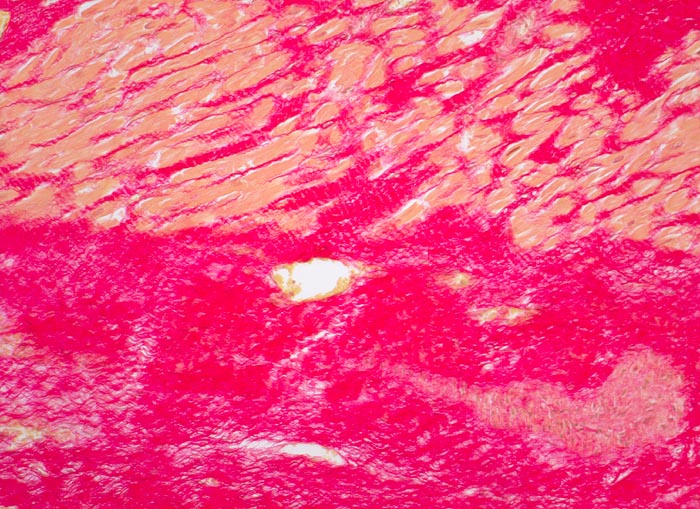

Morphologische Merkmale:

• Herdförmiger Ersatz der Muskulatur durch zellarme rote Kollagenfaserbündel.

• Hypertrophiezeichen der Herzmuskulatur im Randbereich der Narbenareale (verdickte Herzmuskelzellen mit vergrösserten hyperchromatischen Kernen).

• Im untersten Biopsiefragment sind die Narbenareale bandförmig subendokardial verteilt. Zwischen Narbengewebe und Endokard findet sich eine schmale Schicht erhaltener Muskelzellen (Ernährung dieser Zellen per Diffusion direkt aus dem Herzblut).